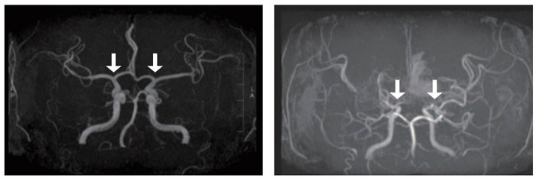

[Слева направо] Мозговые сосуды у здоровых людей и

пациентов с болезнью Моямоя

Болезнь Моямоя — это хроническое прогрессирующее заболевание мозговых сосудов, при котором без очевидной причины постепенно сужаются сосуды в месте разветвления внутренней сонной артерии, снабжающей кровью головной мозг. В результате ухудшается кровоток, и для компенсации недостаточного кровоснабжения начинают развиваться аномальные микрососуды. Однако эти сосуды неспособны обеспечить достаточное поступление крови и склонны к разрывам, что может привести к тяжёлым формам детского инсульта, таким как ишемический инсульт или кровоизлияние в мозг.

До сих пор для окончательной диагностики болезни Моямоя использовалась инвазивная церебральная ангиография, которая особенно тяжело переносится детьми. Существуют также неинвазивные методы, такие как МРТ/МРА, однако они могут переоценивать степень сосудистого сужения и затрудняют детальную оценку сосудов основания мозга, характерных для болезни Моямоя. Это создаёт определённые ограничения в ранней диагностике и точной оценке прогрессирования заболевания. В связи с этим всё активнее поднимается вопрос о необходимости использования жидкостной биопсии (диагностики с использованием крови или других биологических жидкостей).